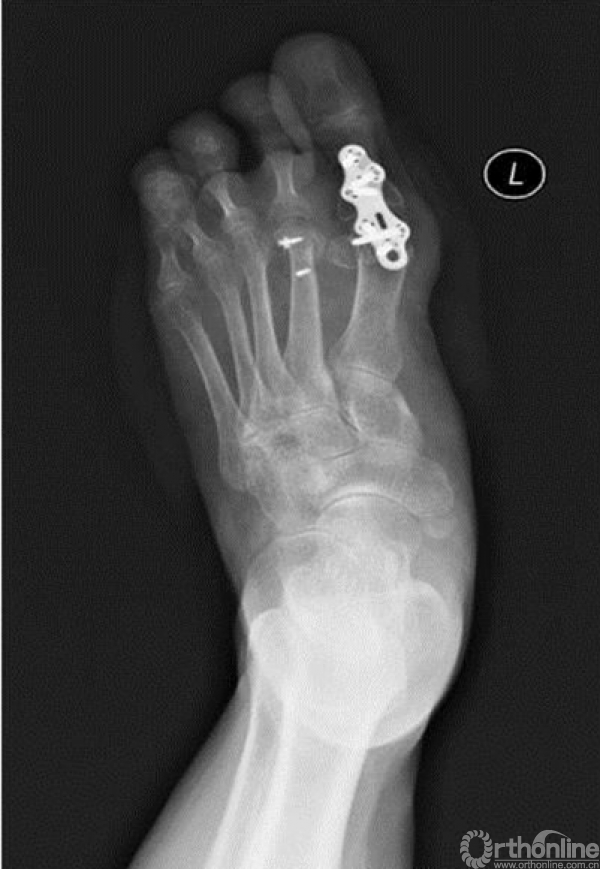

3. X线检查结果

X线检查